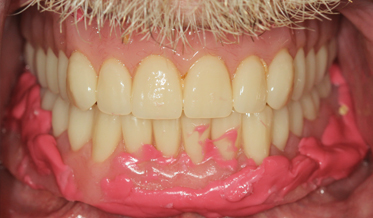

Redefining What Is Possible: Treating Function and Enhancing Esthetics Using a Risk Management System

Kris Swanson, DDS; and Leon Hermanides, CDT